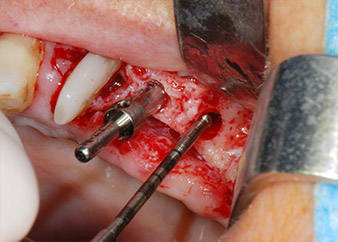

Un mois plus tard, le jour de l'intervention, la douleur et l'inflammation sur la dent 24 étaient minimes mais une mobilité de classe 2 de Miller était toujours observable. Après ouverture des lambeaux et nettoyage des tissus périapicaux et périradiculaires infectés, l'étendue du défaut osseux est devenue parfaitement visible (Figures 2 et 3).

À la racine de la dent, il manquait la totalité de l'os vestibulaire et distal. L'attache était essentiellement limitée à la racine palatine, venant ainsi confirmer le pronostic défavorable initial. La dent 27 présentait également une attache horizontale réduite et une raréfaction apicale minime (cf. Fig. 1), sans symptômes cliniques.

Nous avons toutefois maintenu notre projet initial de conservation des deux dents comme piliers temporaires d'un bridge pendant la période de six mois nécessaire à l'ostéointégration des implants. À la prochaine incision, la situation devrait être réétudiée. Premièrement, afin de gérer le problème endoparodontal, la surface de racine restante a été soigneusement débridée à l'aide d'un équipement piézoélectrique (Piezomed, W&H, utilisé avec l'insert en forme de spatule S1, initialement conçu pour limer la paroi sinusienne latérale) (Fig. 4).